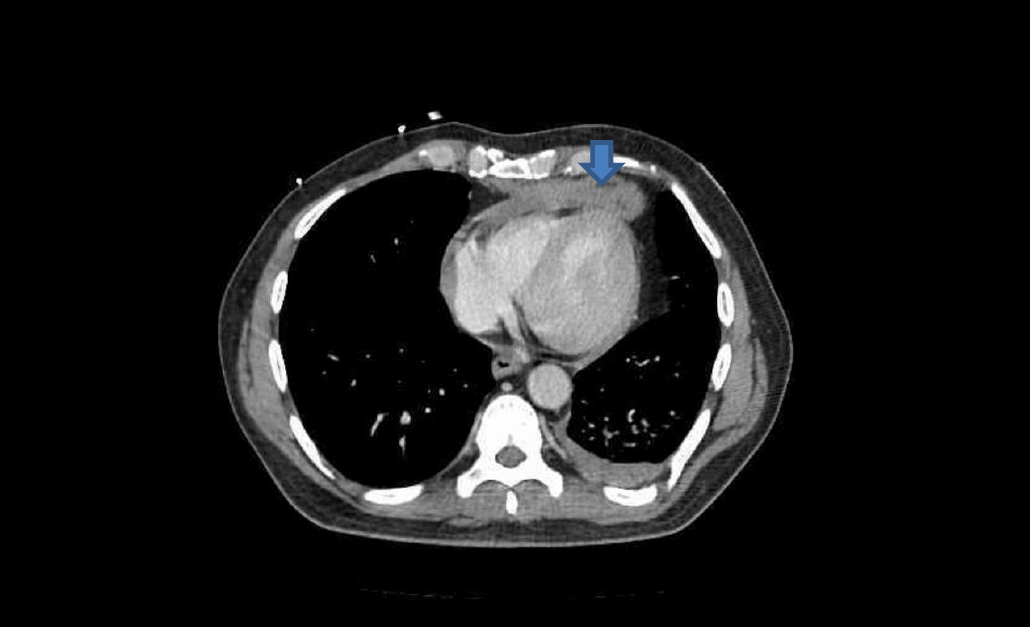

Trauma CT: Blue arrow is contrast ‘blush’=active bleeding point. Red arrow is perinephric haematoma.